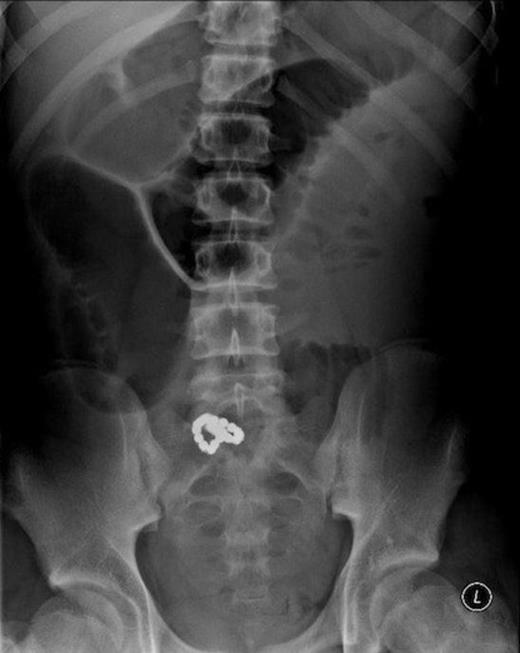

A 16-year-old boy presented via an out of hours GP to a large district general hospital with a 1 week history of mild abdominal distension, vomiting, and worsening central abdominal pain. Examination revealed a soft abdomen with umbilical tenderness. There were no signs of abdominal wall hernia. The abdominal film (figure 1) demonstrated a collection of approximately ten small spherical radiopaque objects positioned in the pelvis. There was evidence of gross small bowel distension proximal to this. The chest film was unremarkable. Considering the radiological findings, the patient was asked specifically about having swallowed foreign bodies. After being showed the abdominal film, the patient reluctantly confessed to having swallowed several metallic balls approximately 4 to 6 weeks beforehand. Inflammatory markers were all within the normal range, and the patient remained cardiovascuarly stable and afebrile.

Pre-operative plain abdominal radiograph showing a chain of small magnetic balls within the small bowel with bowel obstruction.